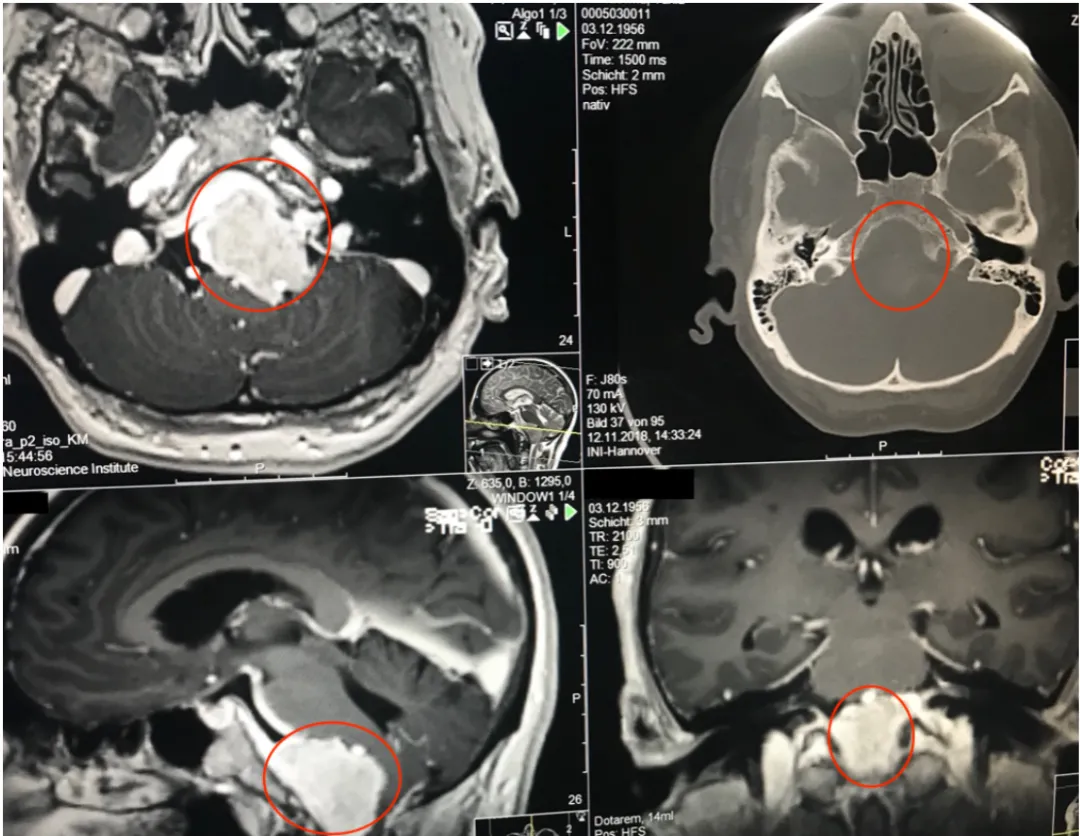

一名40余岁女性患者持续一年多的症状进行性加重,相继出现头痛、复视、肢体无力和吞咽困难等表现。当地医院诊断为岩斜区巨大脑膜瘤,辗转多家医疗机构均被告知手术风险较高、术后并发症发生率高。后寻求INC巴特朗菲教授手术治疗,实现肿瘤近全切,未出现相关手术并发症。

术前MRI显示:岩斜区巨大脑膜瘤压迫脑干和颅神经,侵犯基底动脉